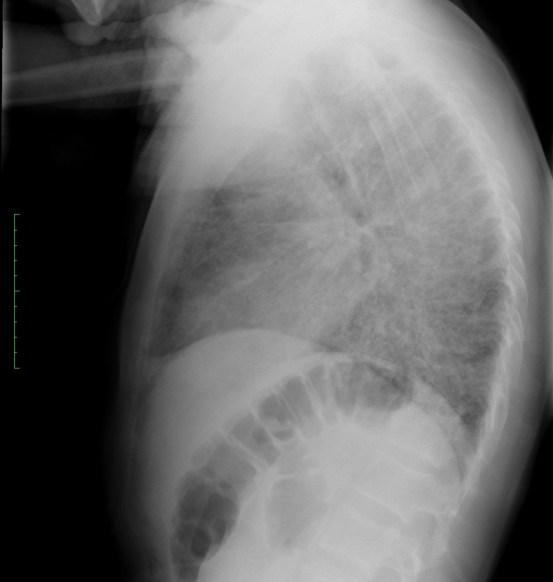

CASO: Operada de esofaguectomia y reconstrucción con coloplastia hace 3 meses. Sintomas de neumonía.

Hallazgos:

- De inicio llama la atención una densidad practicamente total del todo el hemitórax izquierdo, lo cual podría hacernos pensar que estamos ante una posible neumonía.

- Sin embargo el tórax está no está bien centrado, observar como la clavícula izquierda se encuentra casi en la mitad del pulmón, por tanto lo que vemos blanco es el mediastino ya que el tórax está rotado.

CENTRAJE:

El correcto centraje se determina comprobando que las extremidades internas de ambas clavículas equidistan de las apófisis espinosas vertebrales.

Mismo paciente, al cual esta vez se le ha tomado una radiografía en PA y en sedestación. Observar como las clavículas están equidistantes a las apófisis espinosas y como ha desaparecido el velamiento del pulmón izquierdo.

Por otra parte, paciente presenta una cardiomegalia y un discreto ensanchamiento del mediastino es probable relación con cambios postquirúrgicos.